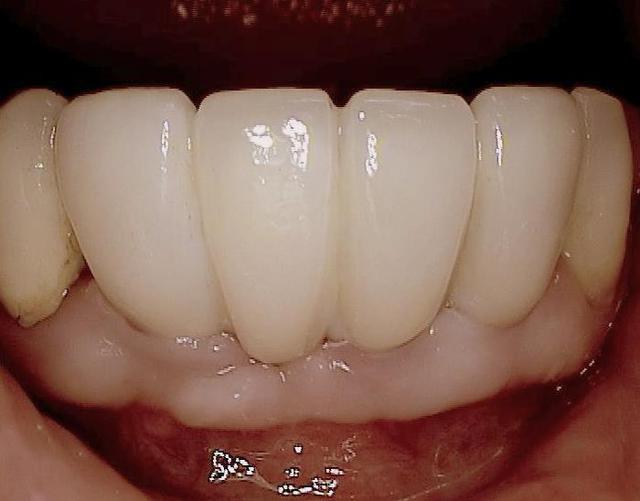

Oui tu as bien raison :-) Ci joint quelques photos en rapport avec ta question ....

c est une bonne question (merci de m avoir expliquer le sens de chiffonne :-) l expression est marrante)

une bonne hygiène est surtout importante si le patient est malade par exemple suite à un "schlaganfall" (en allemand je ne sais pas le terme en francais)

les "vieux" systèmes deux pièces ont un micro espace de 30 micromètres , ce qui explique que les patients devaient nettoyer péniblement ...

en ceramique il n y a pas d accumulation de plaque donc pas de grandes concentration de bactéries gram negatif et anaerobie.La gencive se forme très bien autour de la ceramique ( la nature est le meilleur architecte!)

si après quelques années les couronnes sont retirées, on voit pas d infection....

pour finir c est sur qu il faut quand même se brosser les dents régulièrement. Les patients reviennent juste deux fois par an pour un nettoyage professionnel...

Les nombreux cas déjà postés montrent que cela fonctionne et au long terme (radios après 10 ans), et que l implantologie peut être "démystifier" ( si le mot existe...) :-)